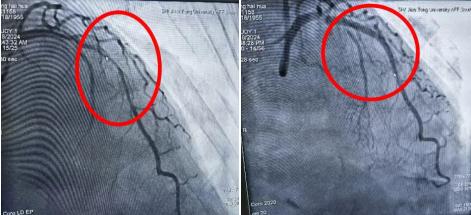

【点击阅读原文】冠心病介入治疗更精准!奉贤区中心医院一次操作实现双模成像2024年7月6日,77岁徐阿姨因为胸痛就诊于奉贤区中心医院心内科,冠脉造影结果并不是大家认为的冠脉狭窄,而是心里藏了两个小偷(冠状动脉瘘)。乔增勇团队选择介入下行冠状动脉瘘弹簧圈封堵术,术后造影提示瘘口被封堵完全。术后徐阿姨冠脉的血不再被偷走,胸痛也消失得无影无踪。